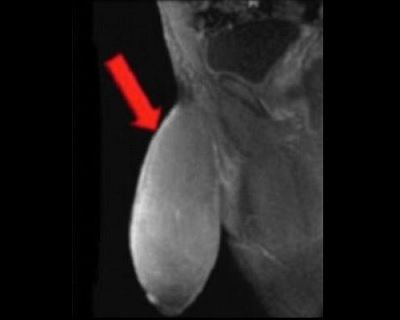

Πριν την χειρουργική επέμβαση οι γιατροί είπαν, σύμφωνα με την MailOnline, ότι το πέος του είχε το μέγεθος μίας μπάλας του ράγκμπι ή ενός γκρέιπφρουτ και ότι ήταν η πρώτη φορά που κάποιος ζητούσε να μικρύνει το πέος του.

Ο 17χρονος, παραπονιόταν συνεχώς μιας και δεν μπορούσε να κάνει όσα έκαναν οι συνομήλικοι του, ενώ με το παραμικρό πονούσε.

Μάλιστα, όπως λέει το πέος του ήταν τόσο μεγάλο που δεν άλλαζε κάτι όταν είχε στύση ενώ είχε φρικτούς πόνους.